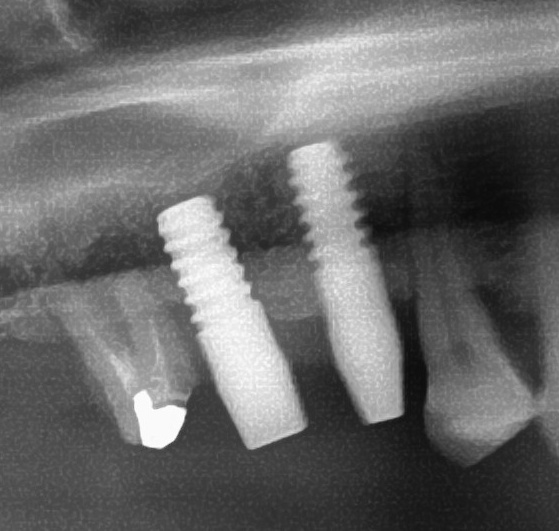

しっかりとインプラント埋め込まれた後は、動揺がないか、噛んだ時に当たらないかなどを確認して、最後にパノラマ写真を撮影して今回のオペは終了となりました。